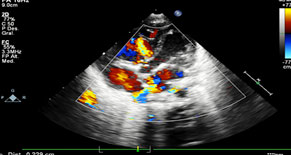

Neurológico: hipoactivo, reactivo a estímulos externos, con fontanela anterior normotensa, la posterior amplia. Al décimo día, crisis convulsivas focalizadas a miembros superiores, se agrega anticomisial, ultrasonido trasnsfontanelar normal. La frecuencia cardiaca con 42 a 65 latidos por minuto, precordio hiperdinámico, soplo sistólico en 2° Espacio Intercostal Izquierdo grado II/VI, sin irradiación, con 2do ruido intenso, borde hepático a 3 cm por debajo de reborde costal, pulsos amplios en las 4 extremidades, simétricos, ameritó apoyo aminérgico y noradrenérgico, persistiendo con bradicardia, por hipertensión arterial sistémica se suspende. El ecocardiograma reportó CIV perimembranosa de 2 mm, CIA de 6 mm ostium secundum, PCA de 5x6x5 mm, insuficiencia tricuspídea moderada y se envía a 3er nivel (figuras 3, 4 y 5). Desafortunadamente no se autorizó autopsia.